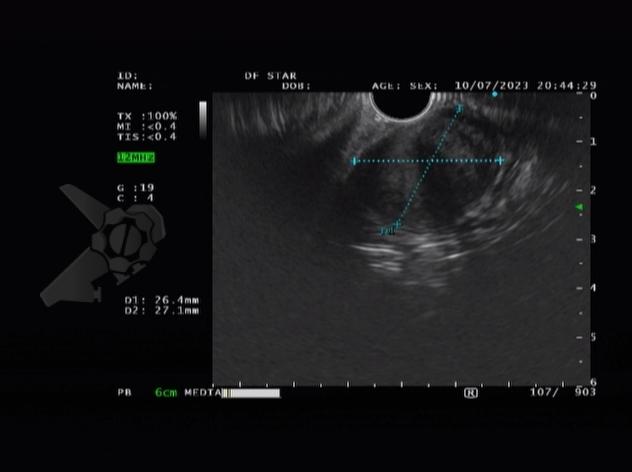

L.R.S., masculino, 8 meses, nascido a termo, com diagnóstico pré-natal de atresia de esôfago com fístula traqueoesofágica distal (Vogt IIIb/Gross C), submetido à correção cirúrgica no 3º dia de vida. Aos 3 meses, passou a apresentar episódios recorrentes de tosse durante a alimentação, engasgos, regurgitação e perda de peso progressiva. A mãe relatou dificuldade em introduzir alimentos sólidos e episódios recorrentes de infecção respiratória nos últimos dois meses. Solicitada endoscopia digestiva alta, que evidenciou estenose puntiforme da anastomose esofágica. Iniciada terapia endoscópica com dilatação esofágica utilizando vela de Savary-Gilliard. Foram realizadas 4 sessões com intervalo de 2 semanas, com melhora progressiva da aceitação alimentar e ganho ponderal adequado. Após a 4ª dilatação, o paciente encontra-se em boa evolução clínica, com alimentação por via oral plena, sem episódios de engasgos ou perda ponderal.

O diagnóstico deve ser suspeitado diante de sinais e sintomas como perda ponderal, disfagia, engasgos e infecções respiratórias recorrentes, vindo a ser confirmado através da endoscopia digestiva alta [11].

O tratamento inicial a ser considerado é a dilatação endoscópica, seja com o balão hidrostático ou com a vela de Savary – Gilliard, não havendo diferença nos desfechos, de acordo com a literatura atual, entre as duas técnicas [12]. Entretanto, alguns trabalhos sugerem que a dilatação com balão pode apresentar menor risco de complicações[12,13,14]. Estudos mostram uma média de três sessões de dilatação para a resolução do quadro, sendo estas intervaladas em um período de duas a quatro semanas, a depender da sintomatologia e evolução clínica do paciente, sendo o ganho ponderal um dos fatores clínicos mais importantes a serem considerados [8,13].